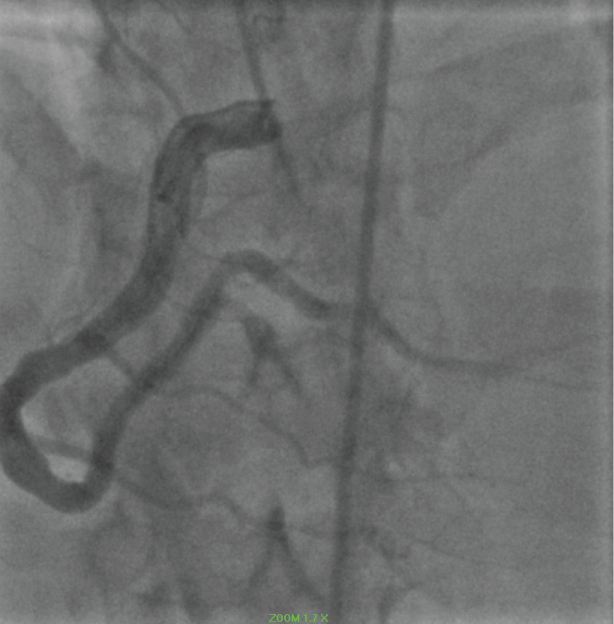

Four years previously the patient had experienced an acute occlusion of his proximal left anterior descending coronary artery (LAD). He underwent thrombectomy and proximal LAD stenting (Figure 2a and Figure 2b).

Figure 2: a) Coronary angiogram LAO view revealing occluded proximal LAD (2014); b) Coronary angiogram RAO post thrombectomy and placement of a 4.0*22 resolute stent (2014). View Figure 2